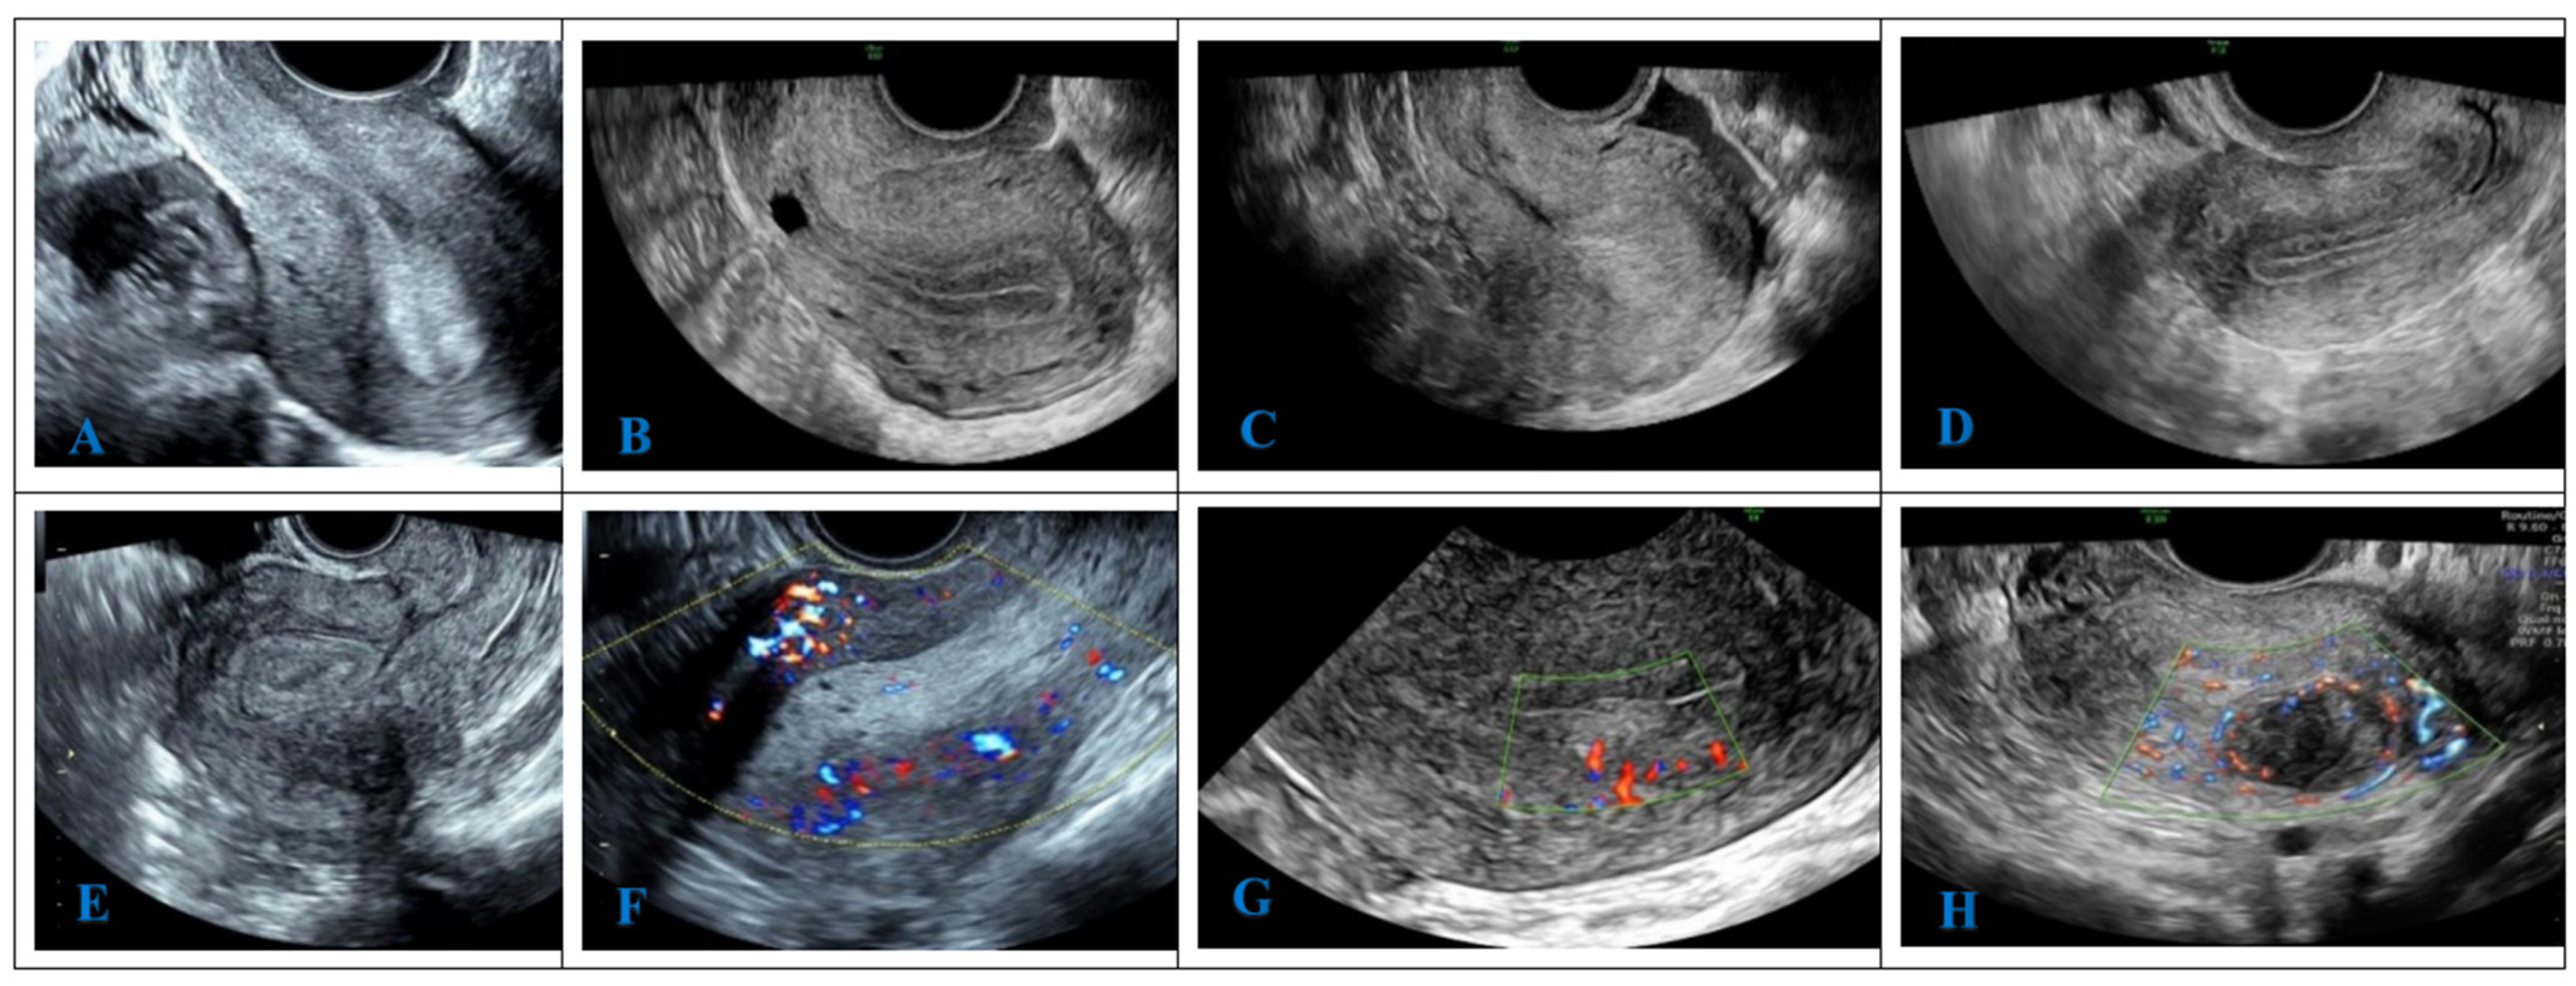

2.8. Ultrasonic Image Analysis